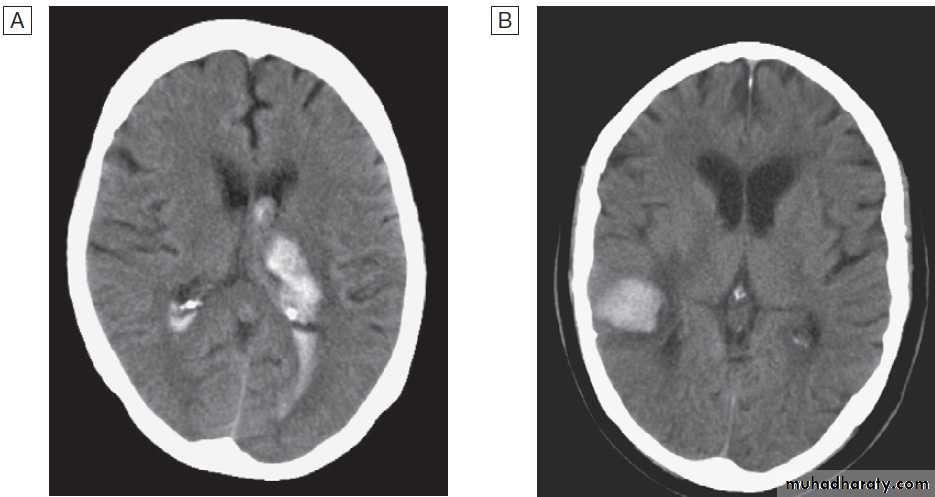

associated risk factorsCT scans showing intracerebral haemorrhage.

A Basal ganglia haemorrhage with intraventricular extension.B Small cortical haemorrhage.